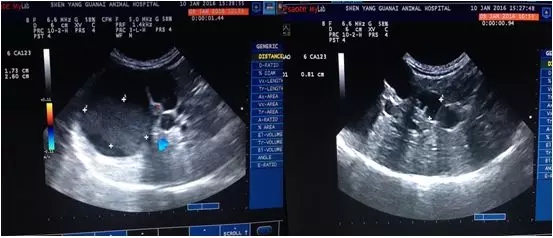

6.影像学检查

超声肝脾肾、胰腺、腹腔淋巴结、腹膜腔未见异常;可见胆囊扩张,胆汁淤积,总胆管扩张直径8mm,部分肝内胆管扩张,肝脏整体回声增高。